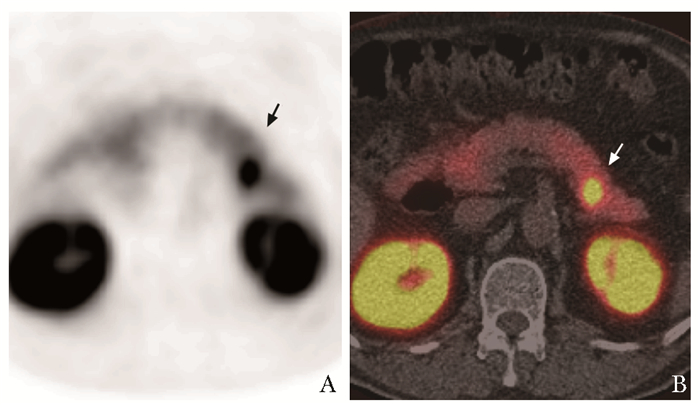

• 摘要: 一例老年男性患者因胰尾部胰岛素瘤反复发作导致低血糖,频繁发作意识障碍,因传统影像学的局限性难以具体定位肿瘤位置,且患者高龄伴慢性肾脏病,外科手术治疗风险较高。经多学科团队讨论后,采用前沿的影像学检查方法和新兴的内镜治疗技术,最终解决了患者的诊治难题。在该例患者诊治过程中,多学科团队应用本领域最新技术共同诊治,体现了多学科协作的重要性。

Abstract: This patient had recurrent hypoglycemia and frequent disturbance of consciousness caused by the insulinoma, but the definite location of the tumor could not be determined due to the limitations of conventional imaging, and he was unable to undergo surgical treatment because of his advanced age and chronic kidney disease. After multidisciplinary discussion, we applied cutting-edge imaging examination and emerging endoscopic treatment techniques, and finally solved the problem of diagnosis and treatment of the patient. This process reflects the importance of multidisciplinary cooperation: various disciplines explore the latest technologies and progress in the fields, and jointly assist in the management of complex diseases.